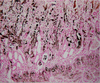

Disease? Pathogenesis? What can this dz cause?

Rubber jaw

Pathogenesis: renal disease –> hyperpohsphatemia –> unstable ratio between calcium and phosphorus –> increased PTH –> increased calcium breakdown of bone –> replacement of bone by fibrous connective tissue

Can cause secondary renal hyperparathyroidism